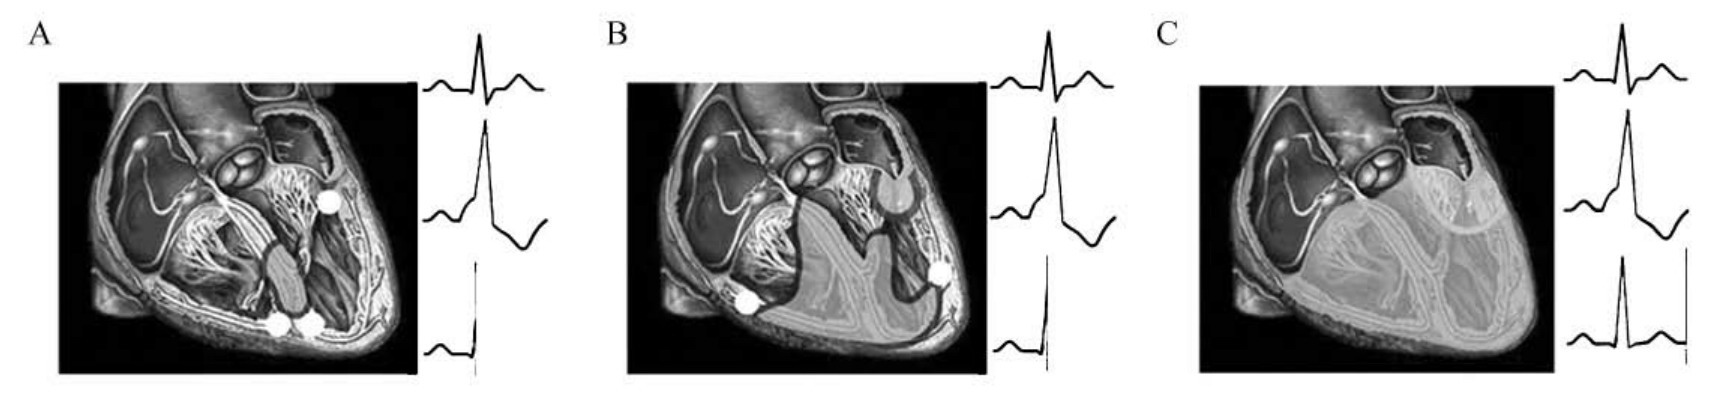

图60-191 不完全潜在性预激综合征机制示意图

A.正路下传略快于旁路(P-R间期正常,无δ波);B.旁路传入心室使连接点处心室提早除极;C.正、旁两路共同除极心室结束,形成单源心室融合波(以终末向量和波形改变为主要表现)